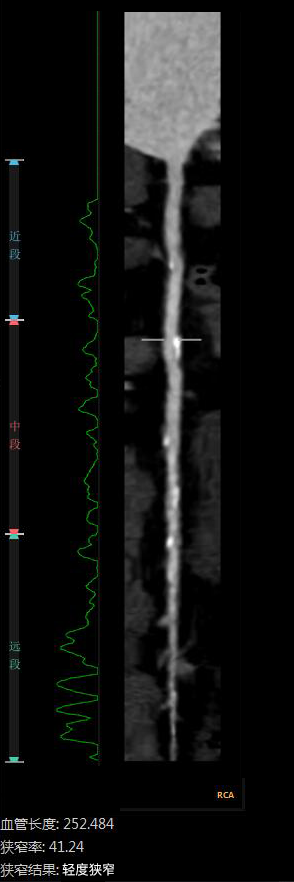

“CTA冠脈全自動(dòng)診斷”

Automatic Coronary Diagnosis

全自動(dòng)量化測量

云端AI的CTA冠狀動(dòng)脈全自動(dòng)診斷

重構了CTA冠脈檢查的極簡(jiǎn)流程

數十倍地提升了工作效率

診斷質(zhì)量得到AI賦能

變得更加穩定、優(yōu)質(zhì)